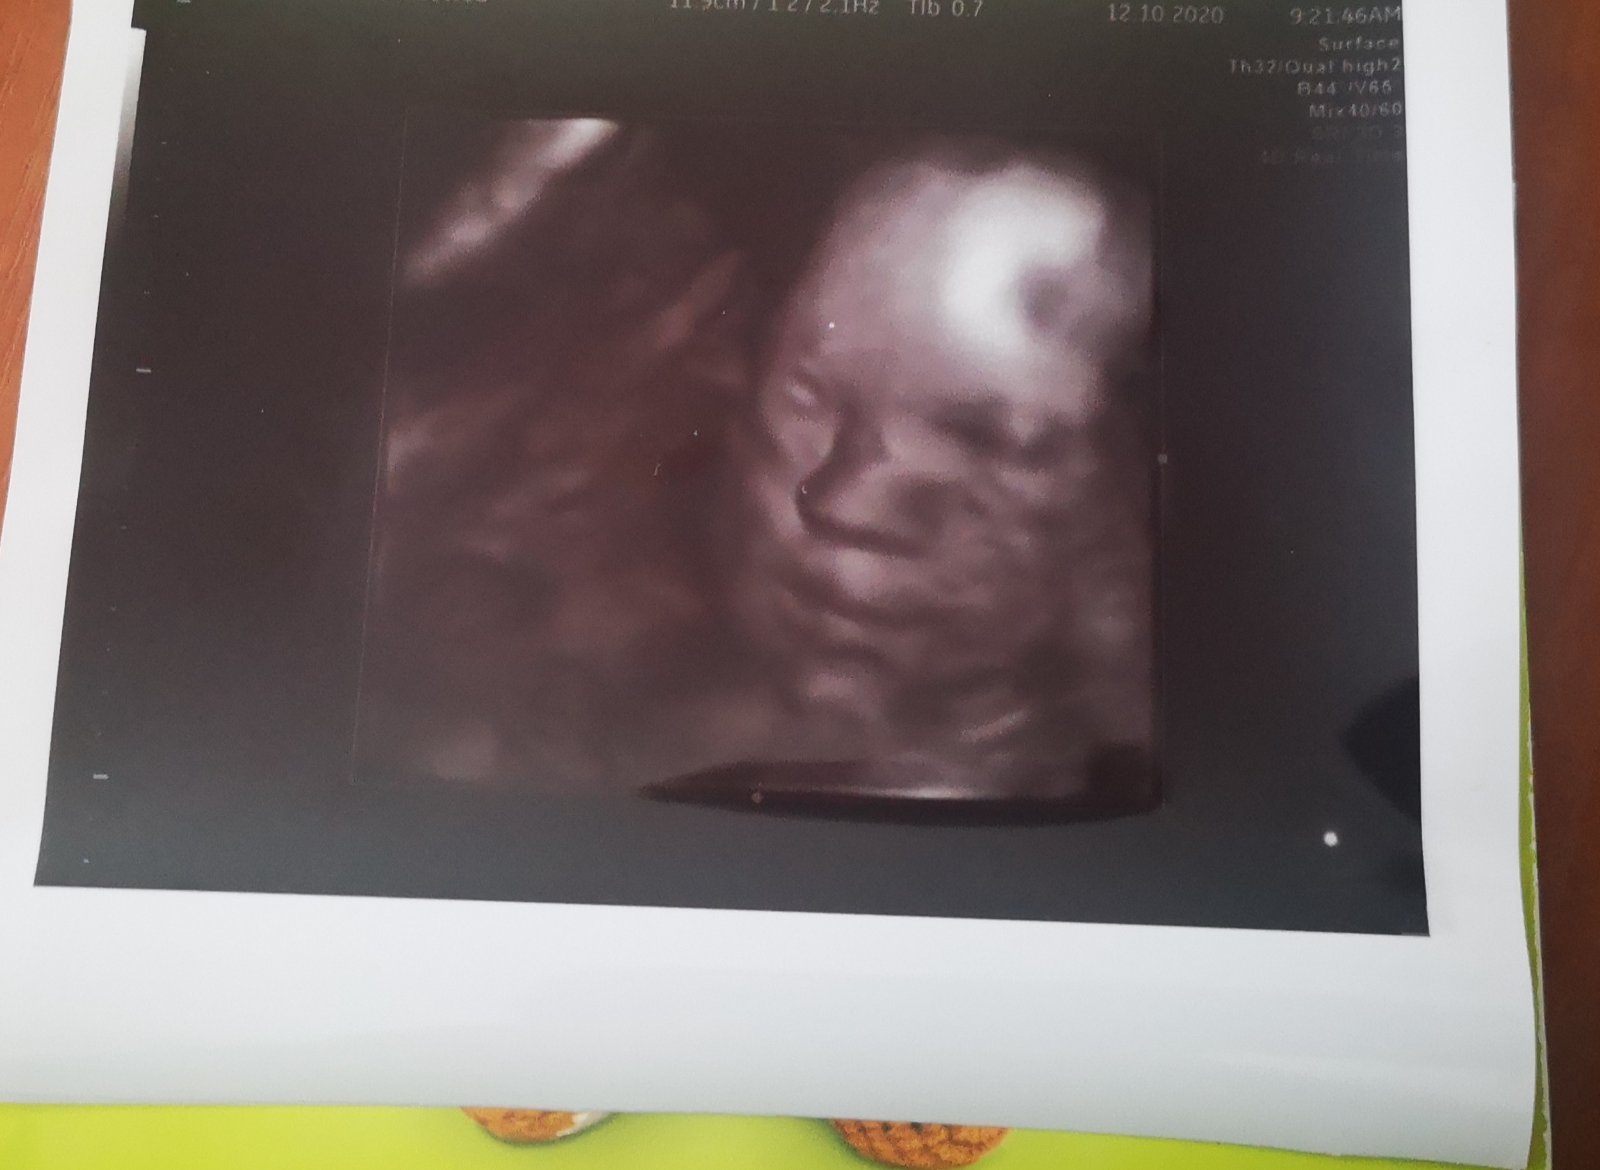

@kessy25 ja som sa tak ukludnit nevedela, revala som asi kazdy vecer, prve o bolo ked sa narodila som sa pytala aky ma nos :D :D ale naozaj, ved aj na tej foto ma pekny nostek (ten skok medzi ockom a nosom) ja som si na nasej fotke toto pozerala dookola ze neexistuje aby tam tie kosticky neboli alebo boli take malinke ked ma pekny nos.

@kessy25 krasny 🙂 ono ti kosti, podla mna, nevie zmerat kazdu samostatne, su hned vedla seba a same o sebe male... keby bola jedna kratsia abo druha tak co by bol ten nostek do strany nakloneny? :D ani v meraniach, v papieroch nepopisuju prava kost, lava kost, ale spoloce ako jeden udaj 🙂 nostek ma krasny